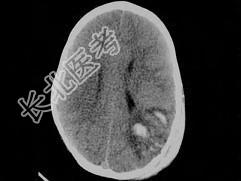

- 单项选择题男,3岁, 头颅被球击中,请结合CT图像, 选择最可能的诊断是  (    )

A、高血压性脑出血

B、脑结核

C、脑挫裂伤血肿形成

D、动脉瘤破裂出血

E、血管畸形